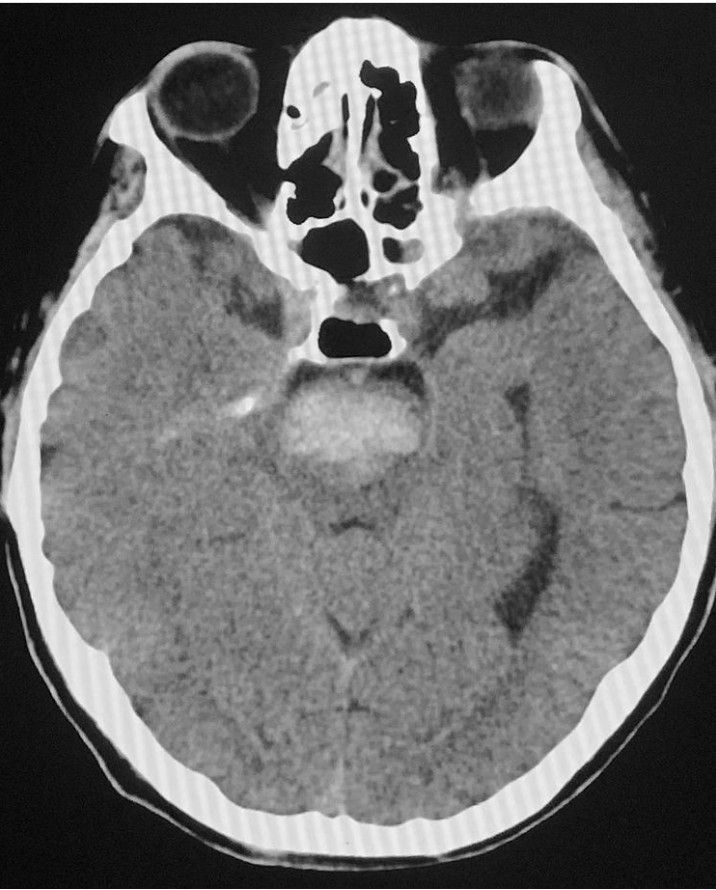

Spontaneous Intra-cerebral Hemorrhage

Here is a radiographical image of spontaneous intra cerebral hemorrhage.